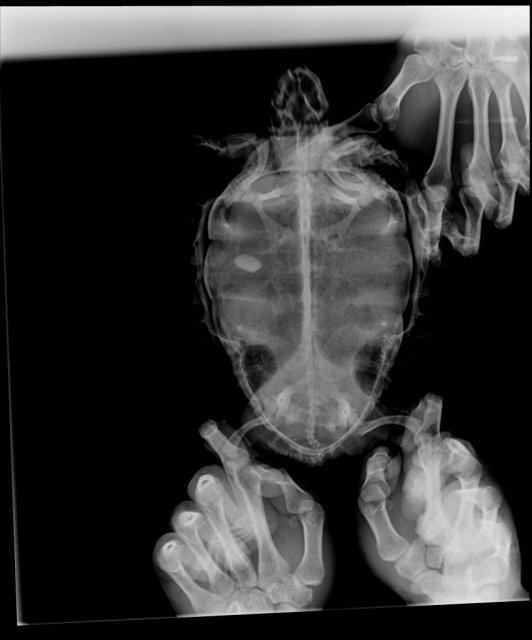

7 лет, не знаем вес длина примерно 12 см. Болезнь в том что не может кажется сделать кладку, куда не позвоним предлагают операцию чего хотим избежать. Черепаха была беременна и не ела около месяца, позавчера пыталась копать и мы наложили наполнителя хомяка растопив водой для влажности по всем углам и в емкость, обычно не выпускали ее но она буквально выпрыгивала из террариума. Потом прекратила искать место хоть и были выделения воды из клоаки, кружение на месте и копание, меняла места но так и ничего не отложила. Мы вернули в аквариум и она была очень спокойна в нем. Подозреваем дистоцию, инородное тело на рентгене но куда не обратимся предлагают операцию. Есть ли возможность ждать яиц, или купить уколы, препараты. Читали о смерти черепах на операциях а люди которые ничего толком не скажут про ситуацию и что можно вообще поделать предлагают только этот выход. Черепаха болела грибком, лечили мазями и после плохих хозяев(моих родителей), когтей нет от этого же, капали бетадин купали в сине. Переодически краснеет под лапами от очень сильного красителя креветок, проверяли много раз что от него но даем редко, он окрашивает даже воду в которой креветку чистим от кожуры

Обращались, Хвостик, пока только рентген делали и это скорее медсестра, имя не знаем. Нет, рекомендаций не было. Рентген не могу загрузить, не хватает 5мб

1539445838_2(2).thumb.jpg.5cf0e6cd299030bbb7510893d2bf9878.jpgРентген загружаю сюда